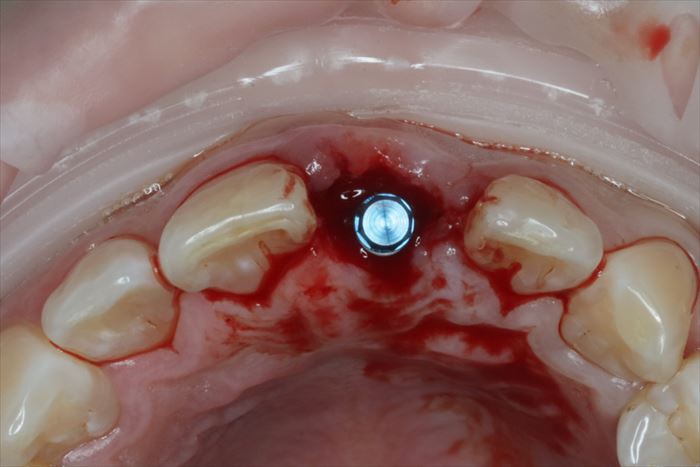

ストローマン社製 BLT インプラント φ4.1㎜ 長さ12㎜ を用います。

インプラントの埋入を終えました。青いパーツはインプラント埋入用のパーツです。

ゆるくならないようにドリリングの見極めが重要です。

インプラントの埋入深度は、想定する歯頚部よりも最低4㎜深い部分にインプラントネックを位置づけます。

前歯のインプラント埋入位置は口蓋側寄りにすることが審美的要件の大原則です。